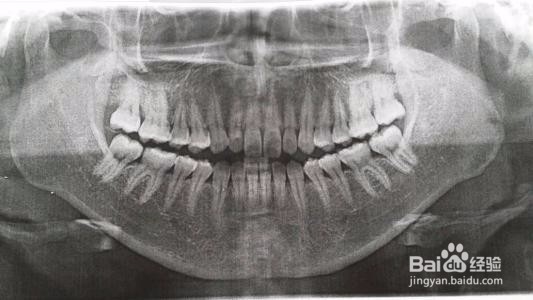

正如上面所说,不是所有的矫正都需要拔牙,矫正是否拔牙需要综合评估牙齿形态、牙槽骨情况、颞颌关节、面型等多方因素。一般牙列拥挤、龅牙、露龈笑等都可能需要拔牙,但像牙齿稀疏这类可能不需要拔牙。拔牙是矫正方案设计很重要的一个环节,多跟医生沟通,选择最适合自己的方案。

矫正拔牙,一般医生会考虑拔除口腔内的患牙,如果口腔牙齿都很健康,多会拔除双尖牙,双尖牙在口腔内的功能使用较弱,拔除不会影响正常的功能性使用。每一颗牙齿都有独立生长的牙槽,拔除不会影响邻牙的健康。所以矫正拔牙没有伤害。